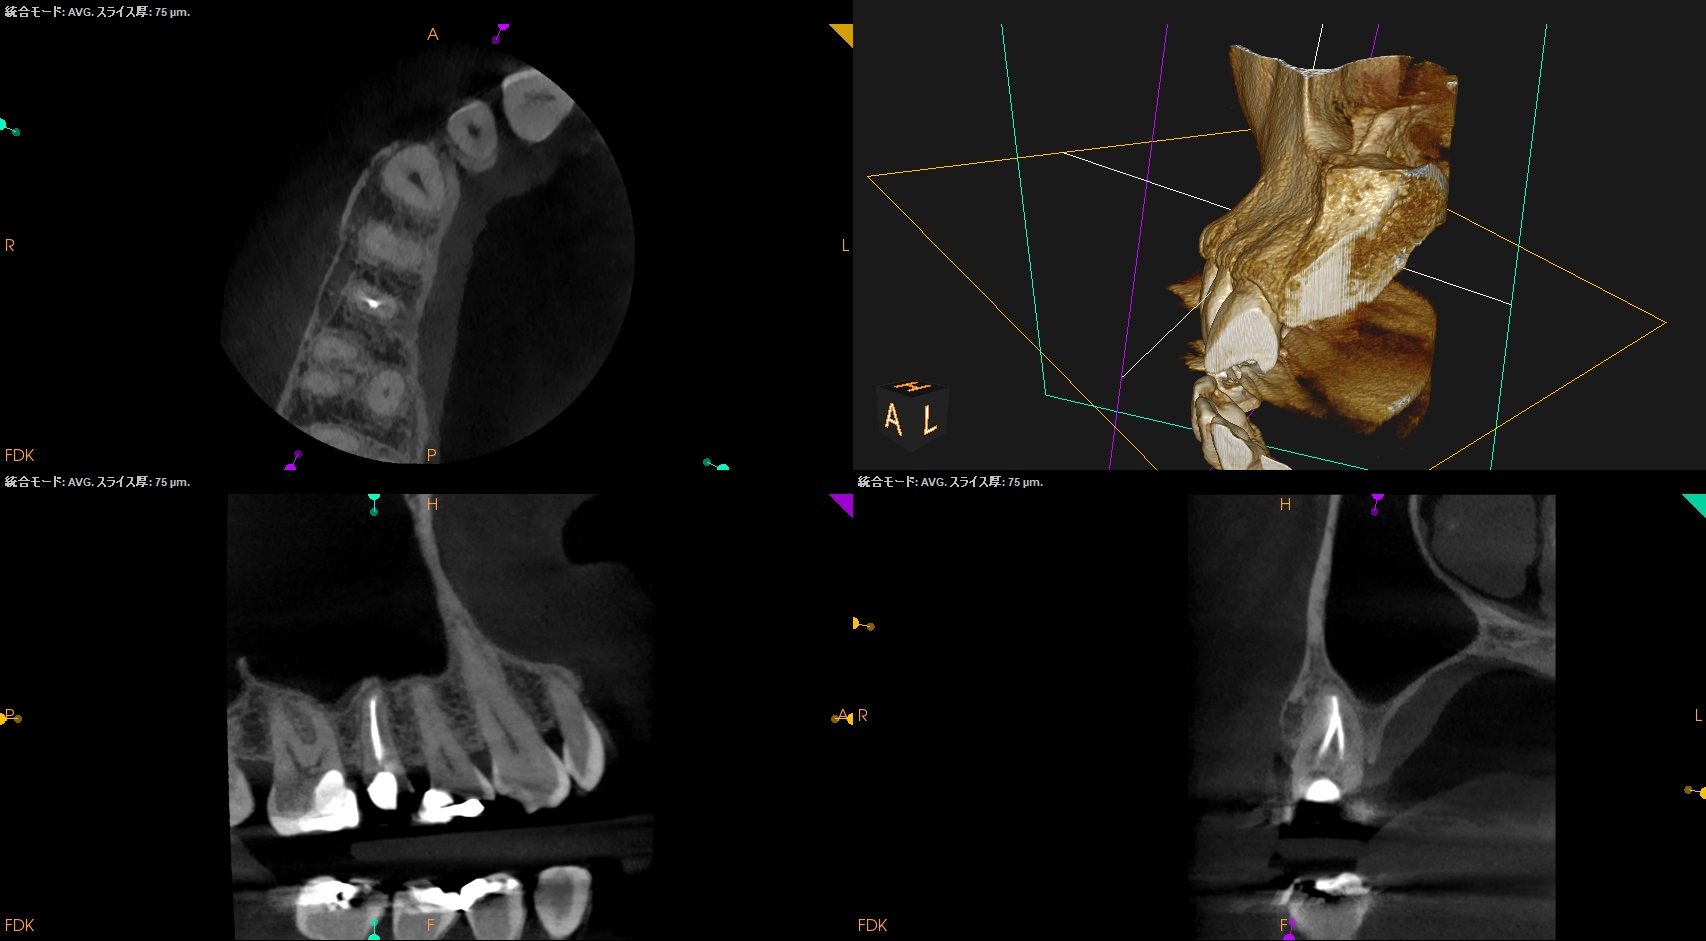

#4 RCT(2025.11.26)

天蓋除去するとBもPも大流血であった。

以下のように作業した。

術後にPA, CBCTを撮影した。

問題はないだろう。

治療は30分で終了した。治療回数も1回だ。

ここに来る前には数ヶ月かかると言われたのに、だ。

次回は半年後である。